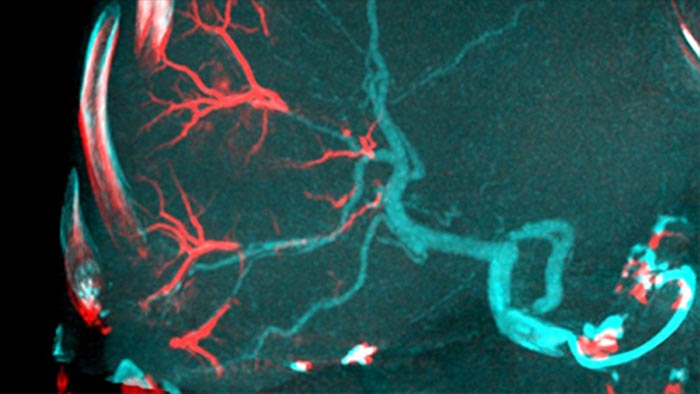

The ability to detect and differentiate hepatic nodules and identify tiny feeder vessels is critical to determining proper therapy. Navigating to the region of interest by reaching all feeders, while remaining selective to the lesion, increases the opportunity for success. Confirmation of treatment endpoint and treatment success while the patient is still on the table boosts clinical outcome confidence.

SmartCT Soft Tissue offers a Cone Beam CT (CBCT) acquisition technique augmented with step-by-step guidance, advanced 3D visualisation and measurement tools; all accessible on the touch screen module at table side.

By opening the arc to the left of the patient, CBCT Open allows off center positioning of the patient table and therefore better centering of the FOV3-4. It significantly increases image coverage to help visualise tumors on the periphery of the liver.4